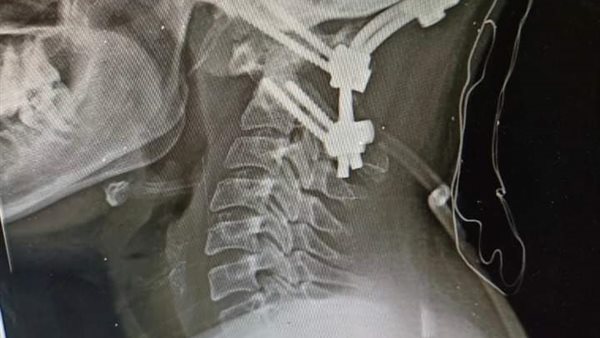

صرح الدكتور مصطفي عبدالخالق رئيس جامعة سوهاج، أن قسم جراحة المخ والأعصاب بالمستشفي الجامعي، نجح في إجراء تدخل جراحي نادراً ويعد الأول من نوعه فى صعيد مصر، لفتاة تبلغ من العمر ١٨ عاماً، وتعانى من مرض خلقى الانغماس القاعدى مع عدم ثبات قاع الجمجمة فى الاتصال بالفقرات العنقية، وهي من الحالات النادرة الحدوث، حيث أدي هذا المرض الي إصابة الفتاة بشلل رباعى حاد نتيجة الضغط على الحبل الشوكي وجذع المخ بقاع الجمجمة.

وقال الدكتور مجدي أمين القاضي عميد كلية الطب البشري ورئيس مجلس إدارة المستشفيات الجامعية، أنه تم على الفور حجز المريضة بالقسم والتجهيز للتدخل الجراحي لتوسيع قاع الجمجمة مع استعدال الاعوجاج الفقرات العنقية وإعادتها الى الوضع التشريحي الطبيعي وتثبيتها بقاع الجمجمة.